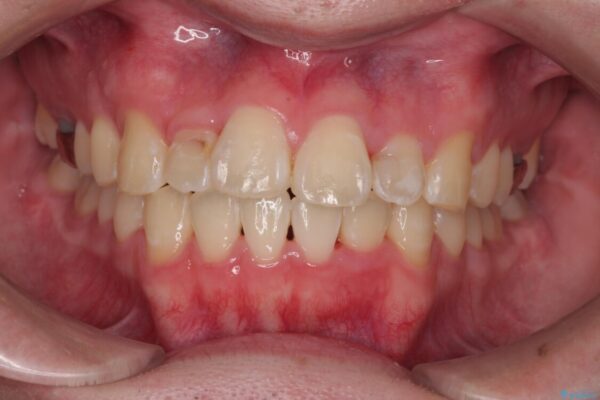

「歯並びがデコボコしていて、上下の中心がズレているのが気になる…」という悩みで来院された患者さまの症例をご紹介します。

初診時の状態

・上下ともに歯がきれいに並びきらず、がたつきが見られました。

・上下の前歯の中心(正中)がずれています。

・特に上顎の幅が狭いため、下顎の歯列も内側に入り込み、歯が並ぶスペースが不足していました。

治療前

• 1年でここまで変わる!歯列のがたつきと正中のズレを改善した矯正治療(メタルブラケット×MARPE) 治療前画像